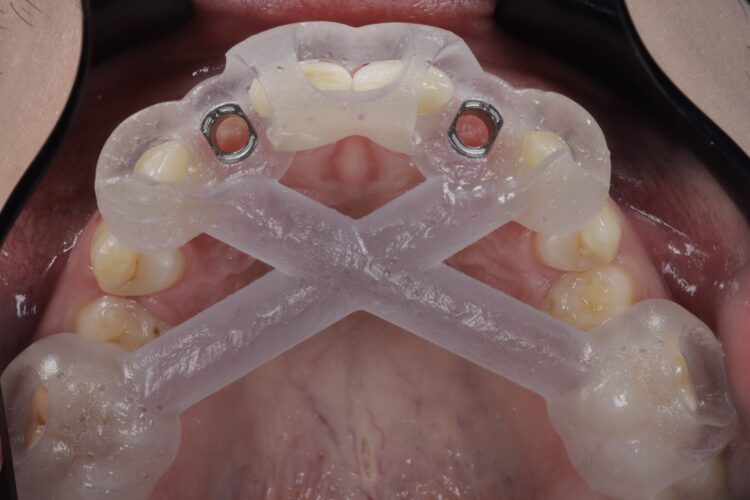

The implant surgery was performed in May 2023 and was filmed live as part of a surgical demonstration for the delegates on a guided surgery course being run by the Fitz Fahey Academy. Implants were placed in the UR2 and UL2 spaces with simultaneous hard and soft tissue grafting. Following the surgery, the patient was provided temporary teeth and instructed to avoid putting undue pressure on the implants during healing.